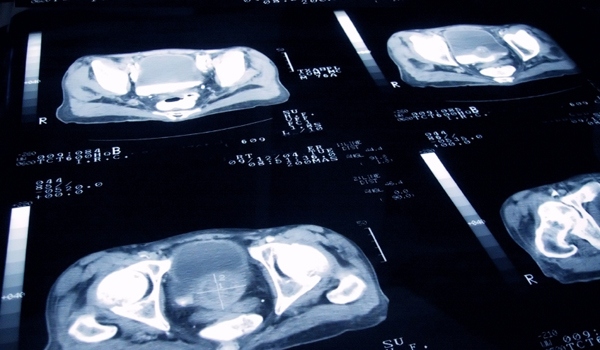

In the new UCSF study, investigators evaluated the ability of the 17-gene assay through prostate needle biopsy specimens to predict pathologic stage and grade at prostatectomy. The researchers focused on whether the test’s biomarkers added independent predictive information beyond what could already be determined about a patient through standard PSA, Gleason grade and biopsy detail variables.